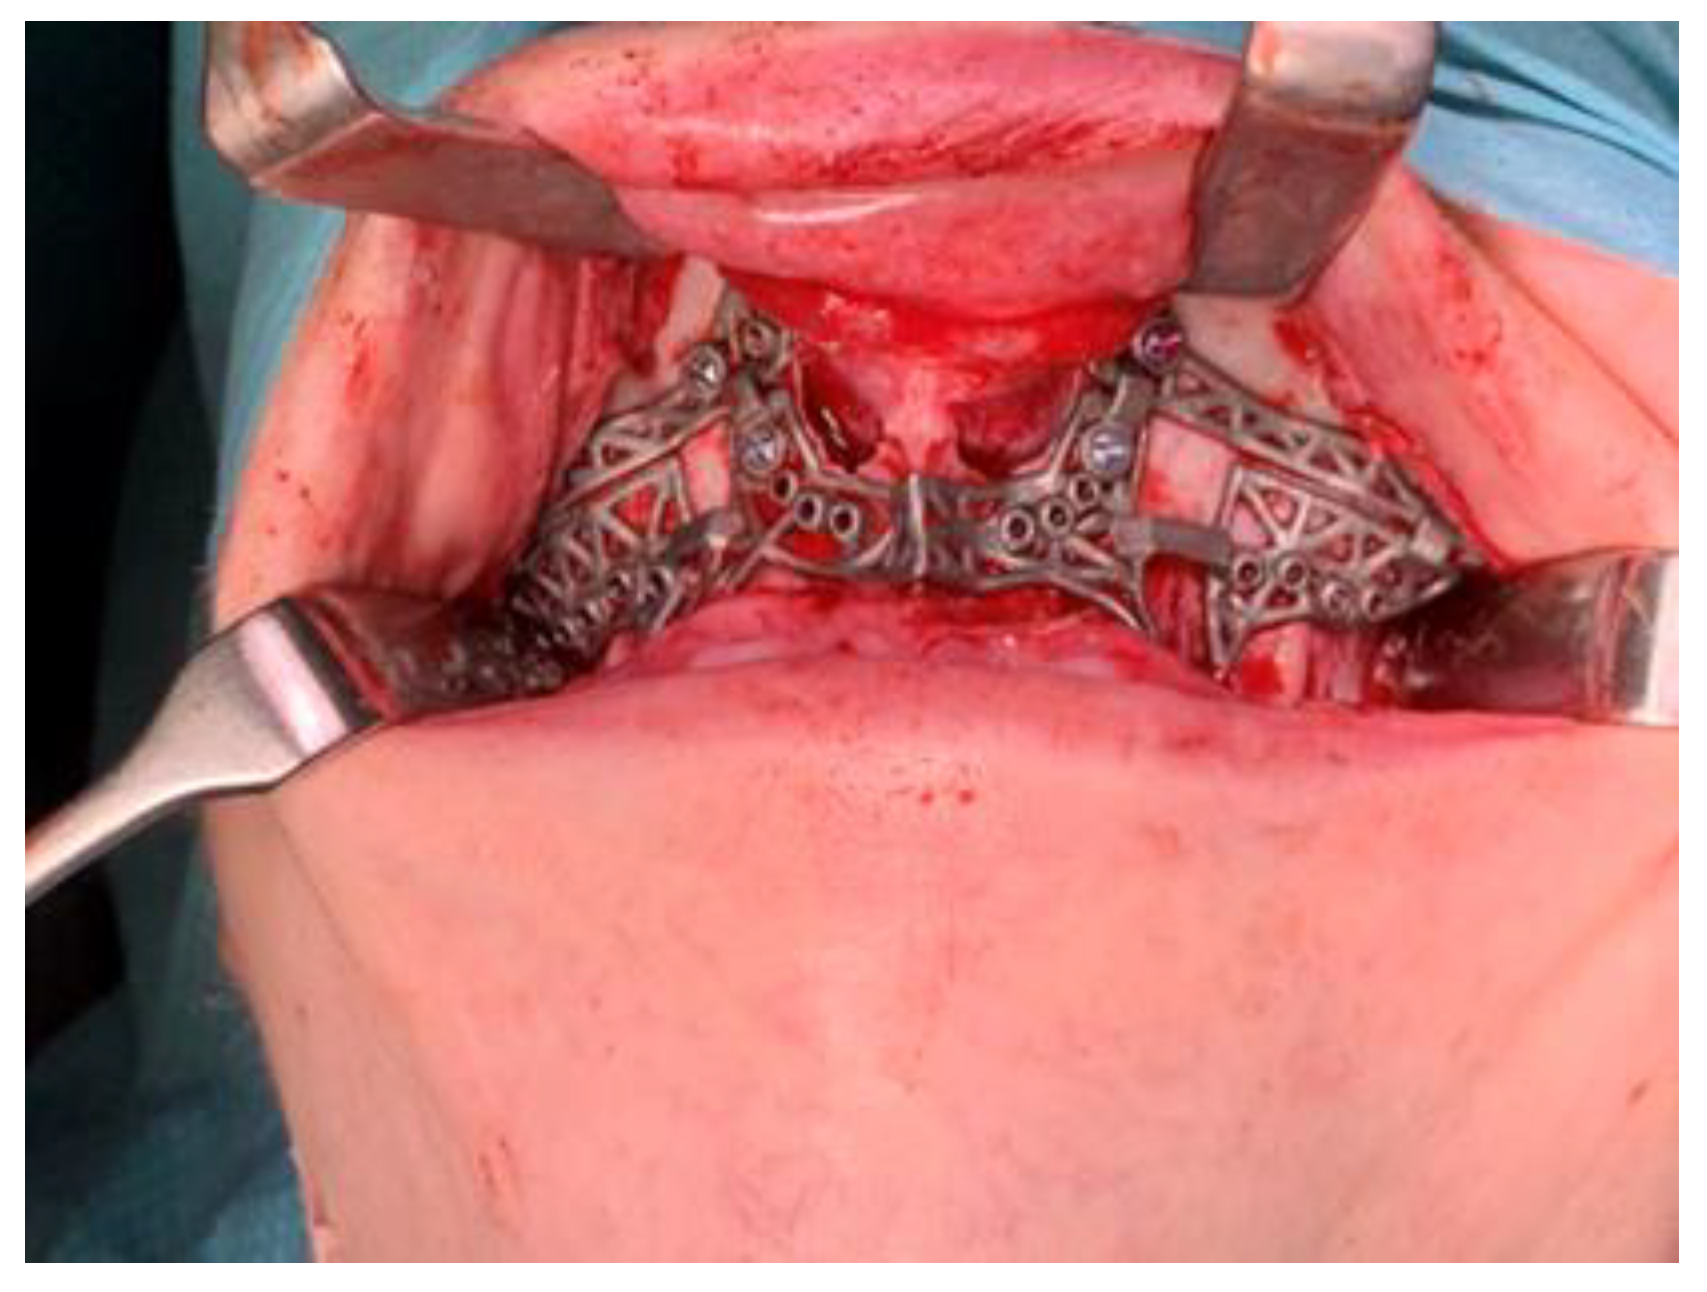

2.3.2. Maxilla